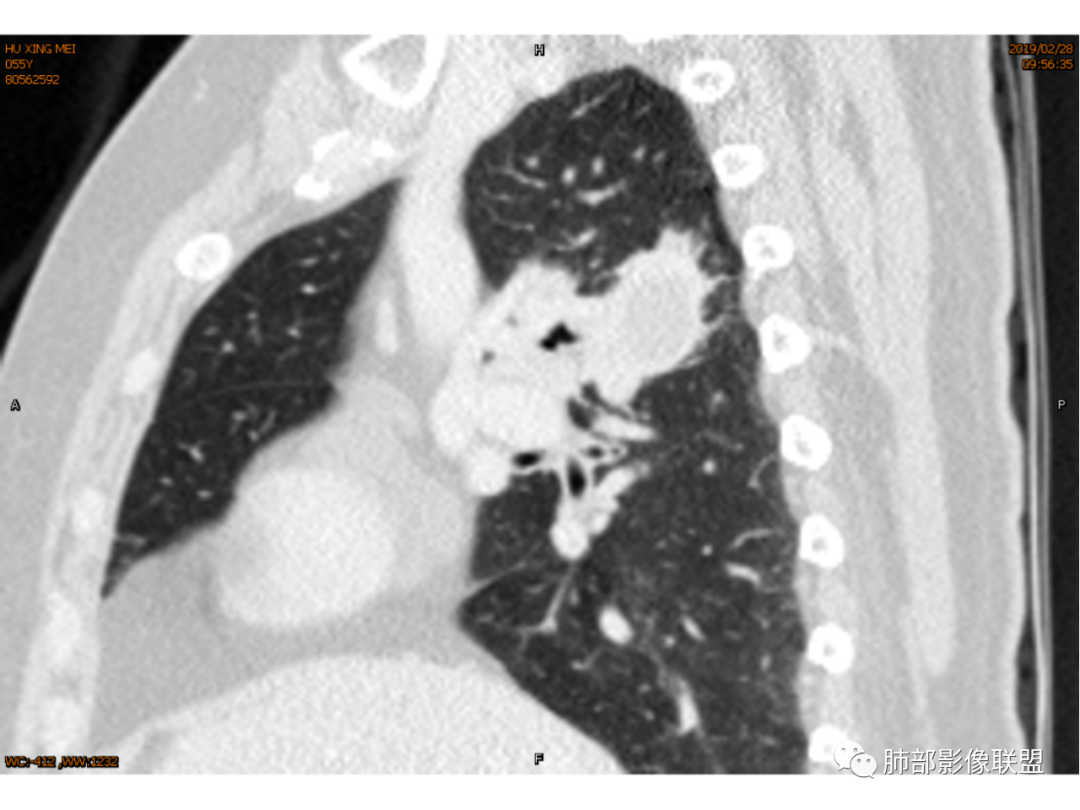

◆ 影像资料:

傅昌瑜:女性,咳嗽咳痰痰中带血1月。血常规、肿瘤标记物正常。CT:右上叶后段类圆形结节,内侧紧贴纵隔,前与右主支气管后壁分界不清。外后部分边缘平直收缩、矢状位可见U型凹陷、桃尖征,周围见边缘模糊的GGO,软毛刺。右上叶后段支气管似乎变狭窄。增强呈薄壁环形强化,内部强化不明显,强化时边缘似见有多个小结节与主病灶融合(芋艿子?)。远端见细小结节。整体考虑炎性病变,结核可能性大,注意鉴别腺癌。

右肺上叶肿块,靠近脊柱,类圆形,部分层面周围有晕,平直、凹陷、膨隆均有,水平位未见明显分叶,失状位重建有棘突/毛刺?局部叶间胸膜增厚,无明显牵拉僵硬,支气管通畅;中心无明显强化,周围环形强化影。临床:女性,亚急性病程,咳血。考虑:倾向良性,结核?

马春平(张家港市一院胸外科):结核+1:右上叶后段小病灶大坏死分隔状、临近支气管壁增厚狭窄

1.女性,咳嗽咳痰痰中带血1月。血常规、肿瘤标记物正常。             2.CT示右肺上叶不规则肿块,边缘以平直收缩为主,可见U型凹陷及桃尖征,周围见边缘模糊的GGO,软毛刺,从形态学的角度病灶更支持炎性改变; 3.增强呈薄壁环形强化,壁光整、清楚,也支持炎性改变;病灶内部平扫CT值密度比较高,约40HU,明显高于水的密度,而且未见强化,提示病灶的坏死可能为凝固性坏死;    4.从上面的分析,病变更符合炎性,患者白细胞不高,治疗后没有好转,不支持普通细菌的感染;影像病灶较局限,边界较清楚,病灶慢性炎症或肉芽肿,形态机发病部位更符合继发性肺结核。患者非易感人群,病灶孤立,尽管有液化,也很难第一时间考虑真菌,尤其是曲霉菌感染。什么是炎性肉芽肿?炎性肉芽肿的常见疾病谱系有哪些?那什么是凝固性坏死和干酪样坏死?跟一般的液化性坏死有什么区别?接下来我们逐一学习一下。